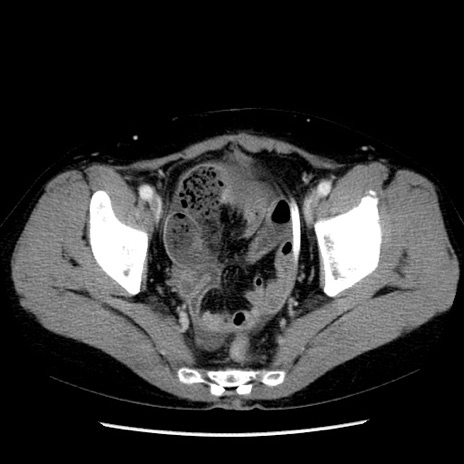

矢状断像